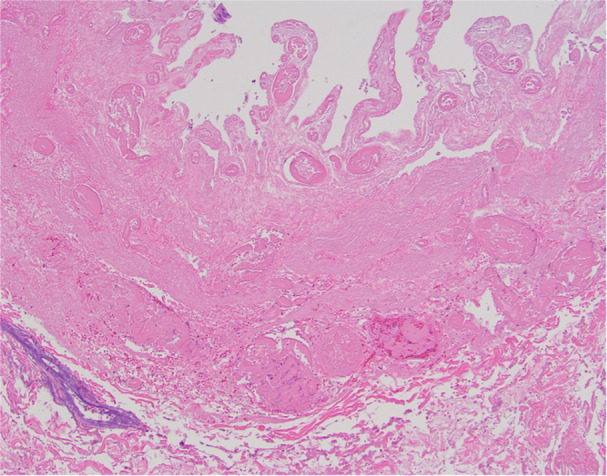

Gallbladder volvulus (GV) involves the rotation of the gallbladder along its axis, resulting in torsion. This pathology is rare, more commonly found in elderly females, but can occasionally occur in pediatric patients. Diagnosis is challenging due to often atypical symptoms, with imaging and laboratory findings typically nonspecific. Prompt surgical intervention is necessary when GV is suspected to prevent significant systemic illness. Laparoscopic cholecystectomy has proven to be safe and effective in pediatric cases. In this report, we present a pediatric case of GV, initially misdiagnosed as viral-induced acalculous cholecystitis, which was effectively managed using laparoscopic cholecystectomy.